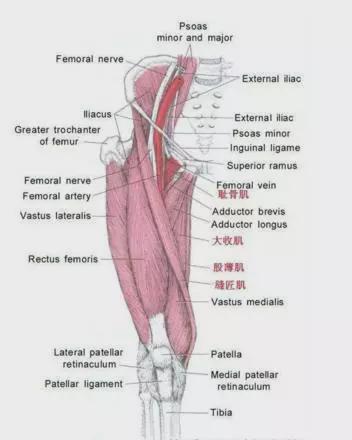

相关肌肉群

大多数膝盖过度伸展并不是天生的,而是由相关肌肉群之间的不平衡引起的。

1.骨盆前部附着两组拮抗肌群:

1)腹部肌肉(腹直肌、腹外斜肌)将骨盆从前向上拉。

2)髋屈肌(股直肌、阔筋膜张肌、髂腰肌、缝匠肌)从前方施加向下的力。

2.骨盆后部附着两组拮抗肌群:

3)腰背伸肌从后面施加向上的力。

4)臀肌(臀大肌、腿筋)将骨盆从后往下拉。

可以得出结论:

膝盖过度伸展=大腿前部肌肉和腿筋肌肉强壮(过度紧张)+腿筋和臀部肌肉无力(过度拉伸)

紧张肌肉1:大腿前部肌肉

紧张肌肉二:小腿肌肉

较弱的肌肉一:臀部肌肉